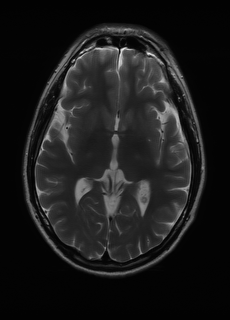

As we observe from the right image in Fig. 2, our BRM, both from MIMO and SISO settings, predicts the performance of dedicated models with a high correlation. We further choose the best three , and perform the last stage of fine-tuning accordingly to (6). A visual evaluation on real data is shown in Fig. 3. For simulated data, please refer to the Supplemental Material section.

Base on the best performing , we perceive that among , , and FLAIR, the results are best when is sampled the most. We suggest that this makes intuitive sense as images provide the best contrast out of the three sequences, which can compensate for the details lost in other images. The same observation can be made on the simulated data, where both and FLAIR show good contrast. When the time setting is changed to non-uniformity, we can see that our search for the best sampling strategy reflects the change. is sampled more as a result of faster acquisition time, while is still sufficiently sampled.

| Sequence | LR | SISO | MIMO | MIMO tuned | GT |

|---|---|---|---|---|---|

(a) 34.38/0.9371

(a) 34.38/0.9371

|

(b) 42.42/0.9883

(b) 42.42/0.9883

|

(c) 44.60/0.9920

(c) 44.60/0.9920

|

(d) 45.50/0.9940

(d) 45.50/0.9940

|

(e) PSNR/SSIM

(e) PSNR/SSIM

|

|

(f) 29.74/0.8903

(f) 29.74/0.8903

|

(g) 36.25/0.9734

(g) 36.25/0.9734

|

(h) 36.42/0.9752

(h) 36.42/0.9752

|

(i) 37.70/0.9832

(i) 37.70/0.9832

|

(j) PSNR/SSIM

(j) PSNR/SSIM

|

|

(k) 39.89/0.9311

(k) 39.89/0.9311

|

(l) 43.94/0.9864

(l) 43.94/0.9864

|

(m) 44.74/0.9883

(m) 44.74/0.9883

|

(n) 45.49/0.9894

(n) 45.49/0.9894

|

(o) PSNR/SSIM

(o) PSNR/SSIM

|